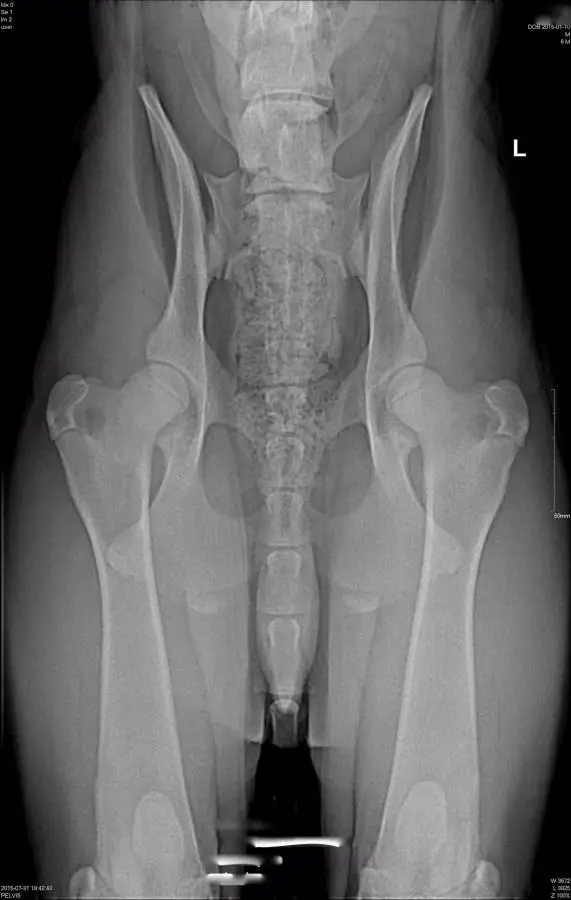

This is one of the best positioned hip xrays we've ever seen on this forum. Your vet did a really great job.

Some members on the German Shepherd forum said his hips weren't properly postponed. Thoughts?

Whoever said that was wrong, cholster. They could not be any better.